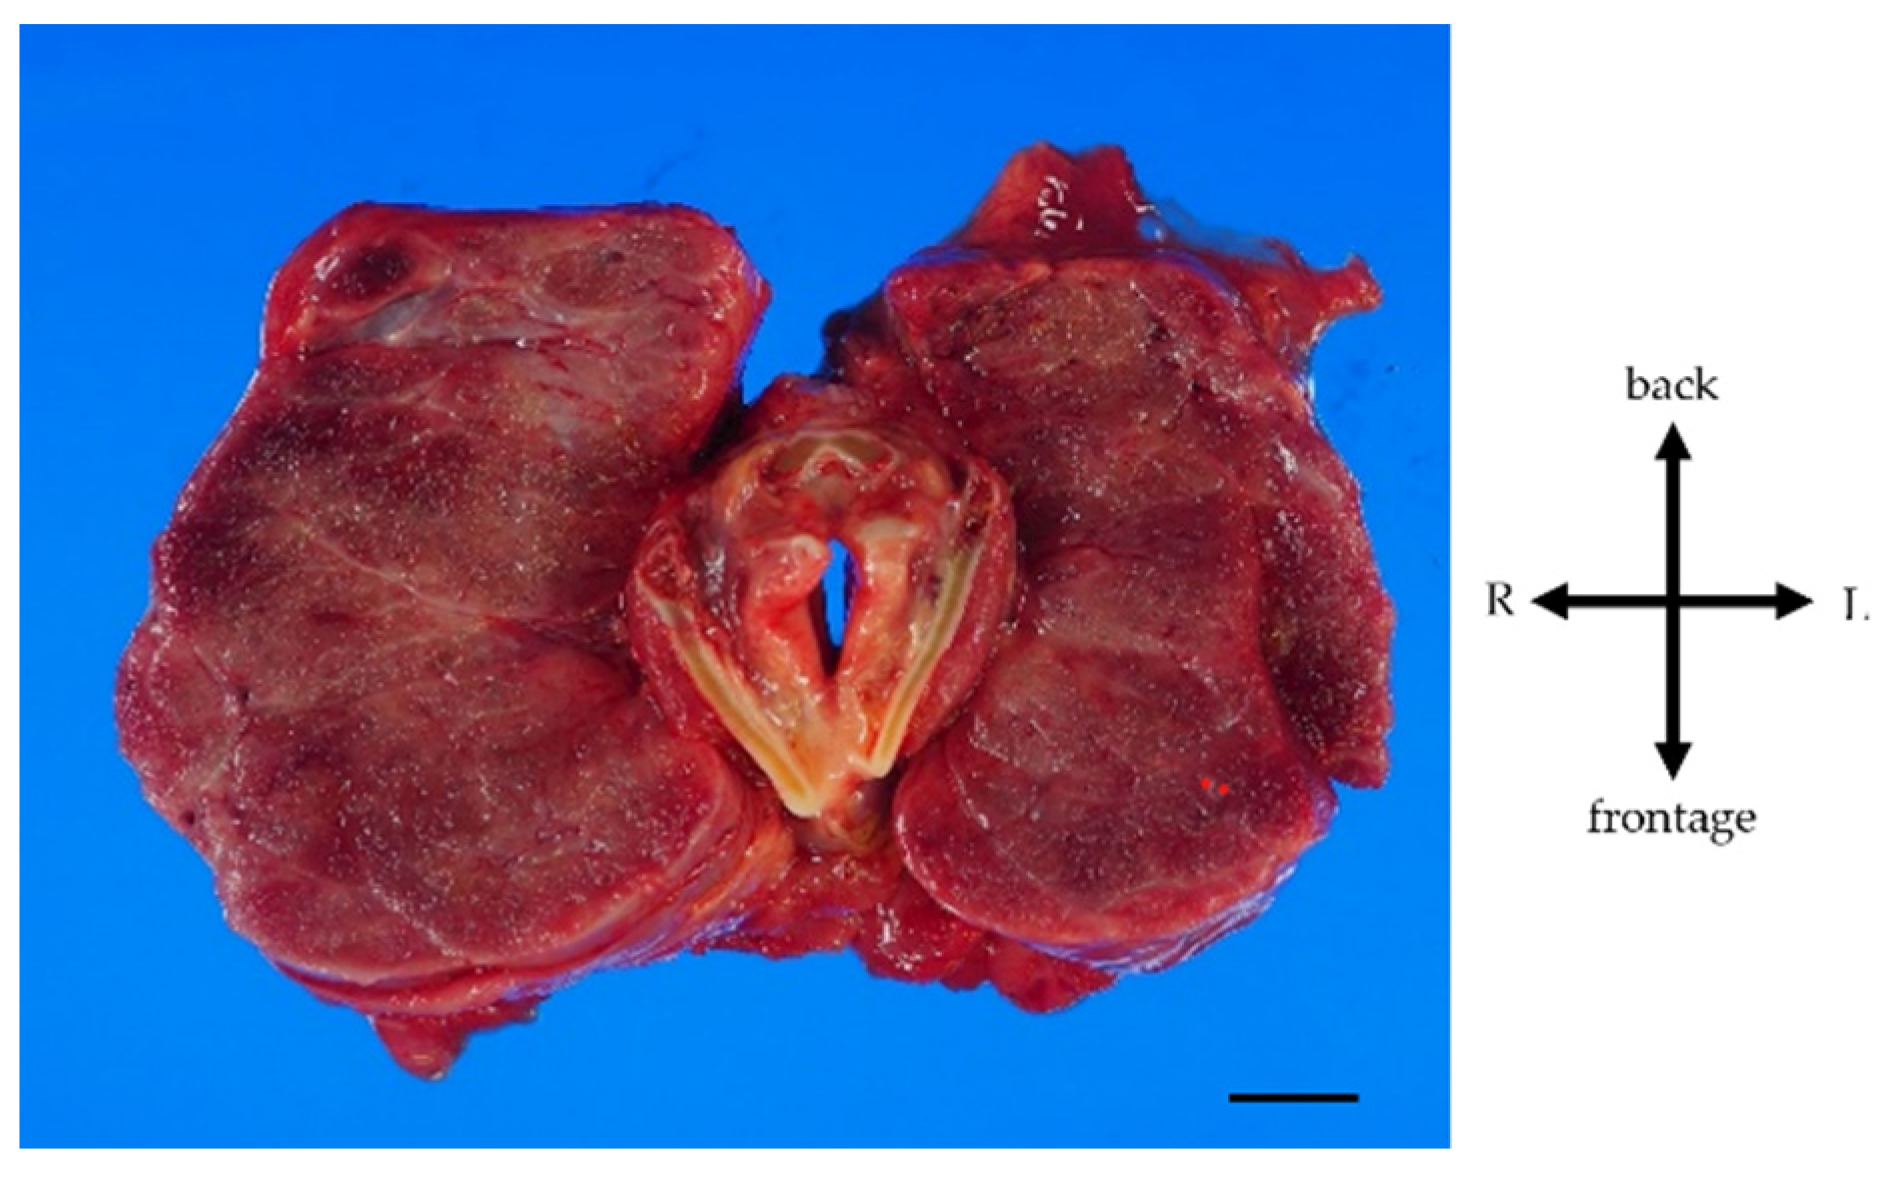

A 34-year-old woman was diagnosed with primary pulmonary hypertension (PPH). At that time, the current IPAH was called PPH. Then she underwent right heart catheterization, and her mean pulmonary artery pressure was 73 mmHg. She complained of dyspnea at rest corresponding to World Health Organization functional class IV. After diagnosing with PPH, she was treated with continuous intravenous epoprostenol. At 37 years of age, she started complaining of neck swelling. Thyroid studies showed Thyroid-stimulating hormone (TSH) = 0.01 μIU/mL (normal range: 0.35-4.94 μIU/mL), Free T3 = 19.88 pg/mL (normal range: 1.71-3.71 pg/mL), Free T4 = 4.86 pg/mL (normal range: 0.70-1.48 pg/mL), thyroid stimulating antibody = 465% (normal range: 0-180%), so she was diagnosed with Grave’s disease and prescribed thiamazole. Epoprostenol at this time was 15 ng/kg/min. Epoprostenol was titrated to decrease mean pulmonary artery pressure in combination with an endothelin receptor antagonist and a phosphodiesterase 5 inhibitor [10]. Epoprostenol maintained at 60-70 ng/kg/min after 14 years of treatment, and mean pulmonary artery pressure decreased to 30-35 mmHg. Thyroid function was controlled by therapy for Grave’s disease using thiamazole and levothyroxine. Nevertheless, her thyroid gland enlargement worsened as epoprostenol was titrated (Figure 1a, b). At 56 years of age, she was admitted to the local hospital due to worsening dyspnea. However, cardiogenic shock and respiratory failure with hypercarbonemia were observed, and she was transferred to our hospital the next day. At admission to our hospital, the patient’s vital signs were blood pressure of 97/62 mmHg, pulse of 117 bpm, and oxygen saturation of 88% with oxygen at 10 L/min through the mask. On examination, the auscultation revealed coarse crackles in her lungs and strider in her neck. Radiography of the chest revealed bilateral pulmonary congestion and airway stenosis (Figure 2a). Computed tomography of the chest also revealed airway stenosis by her giant goiter (Figure 2b). Blood gas analysis on 10 L/min of oxygen showed pH: 7.2, PaO2: 63.7 mmHg, PaCO2: 73.9 mmHg and HCO3-: 28.4 mmol/L, indicating respiratory failure with hypercarbonemia. Thyroid studies showed TSH = 2.265 μIU/mL, Free T3 = 1.52 pg/mL, Free T4 = 0.90 pg/mL. Tracheal intubation was difficult due to severe airway stenosis. Treatment with noninvasive positive pressure ventilation, dobutamine, and noradrenaline was ineffective, and she passed away on the 12th day after admission. Pathological autopsy was performed. Gross thyroid findings included diffuse enlargement (weight 675 g, size 14 cm x 6 cm) and compressive constriction of the upper airway by the thyroid gland (Figure 3). Histological findings of the thyroid gland showed increased thyroid follicle growth and increased colloidal resorption, suggesting a hyperthyroid state (Figure 4). There were no obvious malignant findings. The cause of death was considered to be respiratory failure due to airway narrowing caused by thyroid gland enlargement. The enlarged goiter was thought to be due to continuous intravenous epoprostenol therapy for IPAH.

Figure 3. Gross findings of goiter. Weight of the goiter was 675 g. Size of the goiter was 14 cm x 6 cm. The thyroid gland is symmetrical and diffusely enlarged. Pressure-drainage stenosis of the trachea due to the giant goiter was present. Scale, 1 cm.

We experienced a case of a massive goiter that led to airway stenosis during long-term continuous intravenous epoprostenol therapy. The enlarged goiter of this case doesn’t contradict hyperthyroidism according to Grave’s disease by the pathological findings. It is rare to report the enlarged goiter with airway stenosis by prostaglandin I2 derivatives. There is only one previously reported case of airway stenosis as in this case [11], but pathological findings are not discussed. This is the first case report of airway stenosis by giant goiter due to prostaglandin I2 derivatives which was also pathologically autopsied. There are two mechanisms of goiter by prostaglandin I2 derivatives. First, prostaglandin I2 receptor is expressed in the thyroid follicular cells, and prostaglandin I2 derivatives bind to this receptor and promote thyroid hormone synthesis [12]. Second, prostaglandin I2 derivatives active Th17 cells associated thyroid enlargement and Grave’s disease and promote the autoimmune response [13,14]. Although thyroid function was stable with thiamazole and levothyroxine in this case, her neck swelling was worsened. The cause was thought to be associated with the continuous intravenous epoprostenol therapy. Treatment for thyroid gland enlargement includes surgery or intra-iodine radiation therapy [15]. But it was reported that it was difficult to remove the giant goiter weighing more than 200 g due to the increased risk of hemorrhage generally [16], and the risk of perioperative mortality for patients with pulmonary hypertension is also high at approximately 8.3% [17]. Thus, her predicted perioperative mortality was high. Furthermore, as the enlarged thyroid gland became huge, the need for radioactive iodine became excessive, making oral administration of radioactive iodine difficult. The patient also had severe pulmonary hypertension on high-flow continuous intravenous epoprostenol therapy, making it difficult to interrupt epoprostenol. Therefore, proactive intervention for goiter swelling might be considered in the earlier stages of epoprostenol therapy for PAH.